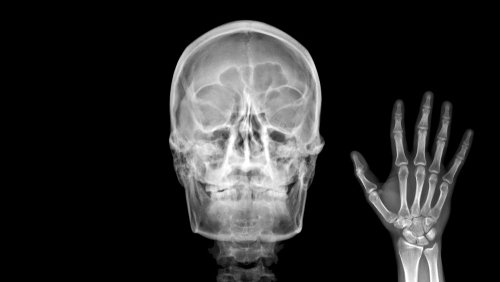

Как проходит рентгенография носоглотки

Сначала администратор уточняет данные, затем рентгенлаборант приглашает в процедурный кабинет. Проведение занимает 5–10 минут, основное — правильно уложить пациента и зафиксировать положение головы. Используется медицинский рентгеновский аппарат с цифровым детектором: так снимок сразу видит врач на мониторе. Возможны следующие варианты выполнения:

- Обзорная. Этот вариант применяют как стартовый. Пациента ставят или усаживают, просят ровно дышать и не глотать. Обзорная рентгенография носоглотки дает общее представление об анатомии: видны контуры кости, носовой полости и тени мягких тканей. Удобно при первичной оценке и в неотложных ситуациях.

- Рентген носоглотки в боковой проекции. Голова слегка поворачивается, чтобы луч прошел сбоку. Такая проекция лучше всего показывает высоту носоглоточного свода, размеры аденоидов, степень перекрытия хоан, дает оценку просвета носоглотки. Именно боковая позиция помогает визуализировать те самые «тени», которые мешают воздуху проходить.

- По Колдуэллу. Пациента просят наклонить лоб к кассете под углом. Проекция по Колдуэллу улучшает видимость лобных пазух и решетчатого лабиринта, а также их соотношение с областью носоглотки. Полезна, когда врач подозревает комбинированный процесс и хочет оценить верхние отделы носа.

- По Уотерсу. Здесь упор делается на верхнечелюстные пазухи и дно орбит. Положение головы с подбородком у кассеты смещает проекцию так, чтобы придаточные пазухи четче отделялись от костных перегородок, а переход к носоглотке просматривался более свободно. Этот вариант часто добавляют к боковой проекции для комплексной картины.

Фотогалерея

Рентген-аппарат